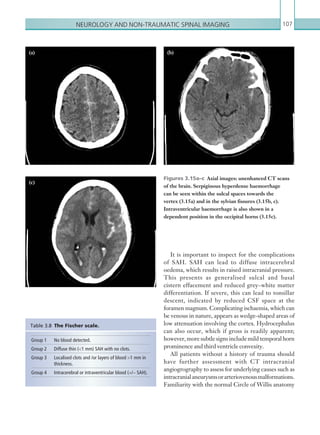

• 101.

Gastrointestinal and genitourinaryimaging 79 This easily identifies calcified renal tract calculi and hydronephrosis (Figure 2.77). It is sometimes difficult to differentiate between phleboliths and distal ureteric calculi in the pelvis; the use of multiplanar reformatting in sagittal and coronal planes can help. Thickening or mesentericfatstrandingaroundtheureterscanindicate recent passage of stones. Contrast enhanced CT can be performed in the portal venous phase. This can be useful for assessing for pelvic/retroperitoneal/gynaecological malignancies, inflammatory aortic aneurysms, and retroperitoneal fibrosis (Figure 2.78) as well as large bladder tumours as a cause for hydronephrosis. Retroperitoneal fibrosis Ultrasound should be the only modality used for suspected hydronephrosis in pregnancy, which can be physiological if present. CT should otherwise be performed if acute hydronephrosis is detected on ultrasound. Computed tomography Hydronephrosis is readily visible on unenhanced and contrast enhanced CT, shown as a dilated pelvicalyceal system (Figure 2.76). In younger patients presenting with pain/haematuria and hydronephrosis, the most likely cause is calculi. In these cases, a plain low- dose kidney–ureter–bladder CT can be performed. Figure 2.77  Axial image: CT scan of the abdomen without IV contrast. A rounded, hyperdense calculus is seen occluding the lumen of the right ureter. Figure 2.76  Axial image: CT scan of the abdomen without IV contrast. The right pelvicalyceal system is dilated compared with the left side. Right renal ­parenchymal volume is preserved. There are mild right perinephric inflammatory changes. Figure 2.78  Coronal image: IV contrast enhanced CT scan of the abdomen in the portal venous phase. Bilateral ureteric stents are noted. Both ureters are thickened with abnormal soft tissue seen at the left renal hlium, suggestive of retroperitoneal fibrosis. ­Subcapsular haematoma is noted adjacent to the left kidney. K22247_C002.indd 79 16/05/15 3:07 AM

• 102.

Chapter 280 RENAL TRANSPLANTDYSFUNCTION Renal transplantation is an increasingly important surgical treatment for end stage chronic kidney disease, negating the need for lifelong dialysis and its complications. A basic understanding of the common surgical techniques and resulting anatomy is essential to allow accurate interpretation of renal transplant pathology. The transplanted kidney is usually situated in the extraperitoneal space in the right iliac fossa. The exact type of arterial anastomosis depends on the nature of the transplanted kidney. Kidneys from living donors are normally grafted via either an end-to-end anastomosis of the donor renal artery and the recipient internaliliacarteryoranend-to-sideanastomosisofthe donor renal artery to the recipient external iliac artery. Cadaverickidneysaretypicallyharvestedwithasegment of aorta, which is attached to the external iliac artery via an end-to-side anastomosis. The venous anatomy is more consistent; the donor renal vein is attached via an end-to-side anastomosis with the external iliac vein. The donor ureter is usually implanted directly into the dome of the bladder. It is important that any potential complications of renaltransplantationareidentifiedasquicklyaspossible intheearlypostoperativeperiod,sincetheycanresultin loss of the graft. Potential complications include renal artery/vein thrombosis, renal artery stenosis, acute tubular necrosis, infection, perigraft fluid collections, hydronephrosis and rejection (hyperacute, acute and chronic). Renal transplant dysfunction should be suspected in the presence of deranged renal function or absence of normalising renal function in the early postoperative period. Other more non-specific symptoms and signs, such as pain, pyrexia, hypertension and anuria, can also be seen. Acute vascular complications, such as renal artery and vein thrombosis, are less commonly seen outside of the perioperative period. While there are some non-specific imaging findings of graft rejection, ultimate diagnosis requires renal biopsy. and inflammatory abdominal aneurysms cause medial deviation of the ureters. Delayed phase contrast enhanced CT imaging opacifies the pelvicalyceal system, ureters and bladder. This technique is useful in detecting ureteric strictures or carcinomas, bladder carcinoma (TCC) and non-calcified calculi. This protocol can be used to differentiate between parapelvic cysts and true hydronephrosis. Discussion with interventional radiology regarding placement of a nephrostomy in an recommended hydronephrotic kidney should be recommended at the end of the report. Key points • First-line investigation should always be ultrasound, on which a dilated pelvicalyceal system is diagnostic. Cortical thickness is important in deciding whether the obstruction is chronic or acute. • CT is very useful in identifying the cause for the hydronephrosis. Protocols should be tailored to the age of the patient and clinical suspicion. Report checklist • Characterise the degree of hydronephrosis as mild, moderate or severe. • Identify the level of obstruction and presence or absence of an impacted ureteric calculus. A focal ureteric calibre change can suggest a pathology even if an abnormality cannot be seen. • Presence or absence of signs of an infected system – this warrants emergency intervention with a nephrostomy. • In cases of hydronephrosis emphasise the need for an urgent urological review. K22247_C002.indd 80 16/05/15 3:07 AM